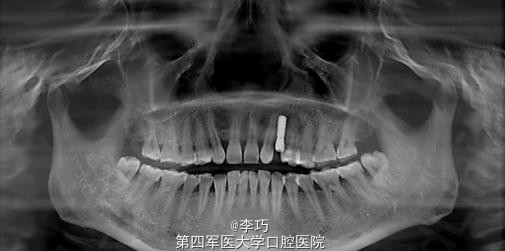

曲面体层片显示乳牙滞留